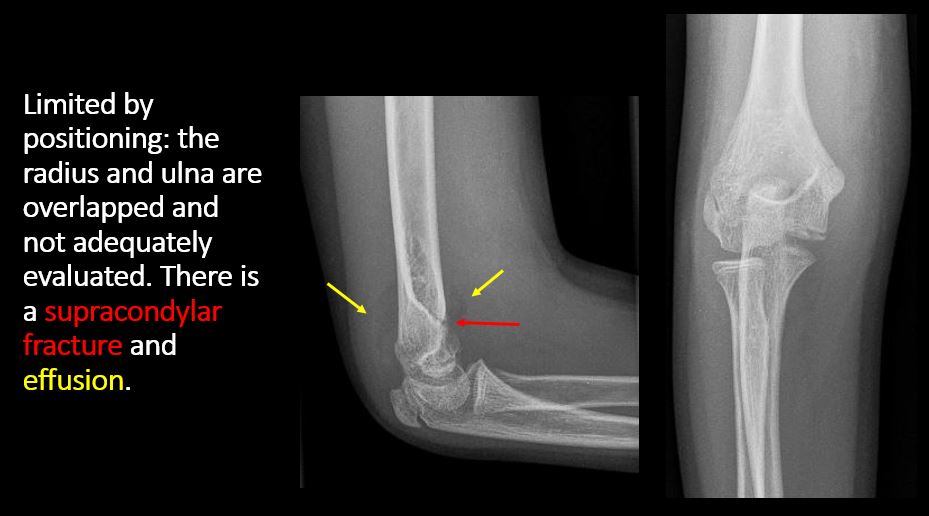

The exam is limited by overlying structures or soft tissues, body habitus, patient positioning, support devices, or motion. |

No | NA |

There is an effusion, fat pad displacement, or fat fluid level. |